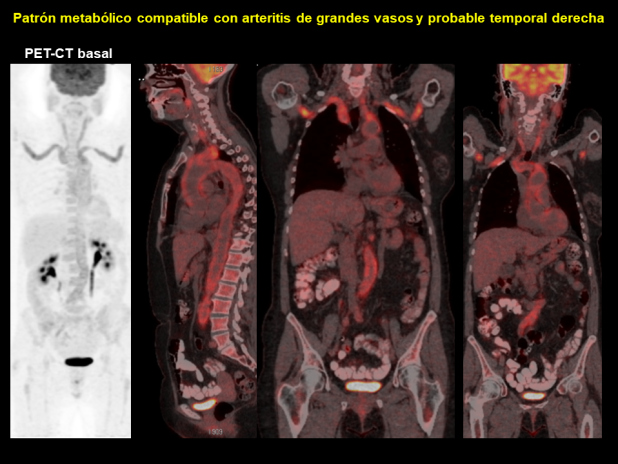

Se realiza PET-CT con 18F-FDG, procedimiento integrado al protocolo de estudio de fiebre de origen desconocido. El resultado muestra aumento de actividad metabólica a lo largo de del cayado aórtico (SUV 7.5), troncos supraaórticos y sus divisiones subclavias-axilares (SUV 6.3-7), carótidas comunes (SUV 5), aorta abdominal (SUV 4.6) y ejes ilíacos (SUV 4.6), interpretándose como arteritis de grandes vasos (Figs. 1 y 2). En la región temporal derecha, coincidiendo con el plano fascial también se identifica aumento de actividad (SUV 3), asimétrico con respecto al lado izquierdo, que se acompaña de alteración de densidad de la grasa, lo que sugiere la presencia de arteritis temporal (Fig. 3).